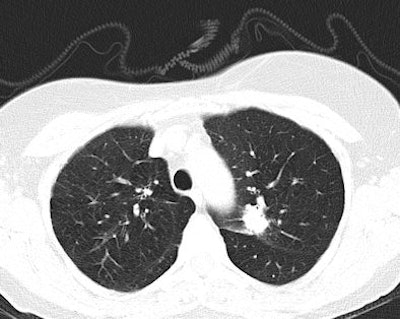

The NLST has shown that lung cancer death rates can be reduced by 20% when a high-risk group is screened with a low-dose CT scan compared with chest radiography. The participants were asymptomatic persons ages 55 to 74 who had smoked at least 30 pack years in their lifetime. Participants received a baseline CT scan and two annual screening CT exams, and were then followed for a median of 6.5 years. Screening of high-risk individuals led to a better opportunity for curative treatment, the investigators found.

"There are many potential advantages of CT screening," Heuvers pointed out. "Low-dose CT is not only a valuable tool to detect lung cancer at earlier stages, it can also be used to monitor other causes of morbidity and mortality in heavy smokers, such as ischemic heart disease and chronic obstructive lung disease (COPD). Early detection of coronary artery calcification could be used to identify patients who are likely to experience ischemic heart disease. In addition, early detection of COPD could signify patients with a rapid progression of their COPD, leading to an intensive treatment."